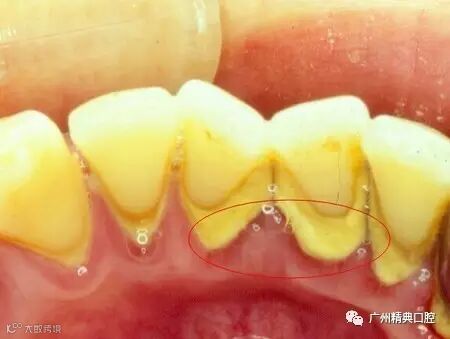

1)龈上牙结石,一般是覆盖在牙缝,牙齿背面牙根处,肉眼就看到。

2)龈下牙结石,这种牙结石就比较厉害了,已经「侵入」到牙龈下面了,一般会出现「牙龈出血」「牙龈肿痛」等情况,我们肉眼是看不到的。

A:照照镜子,如果发现牙齿内侧牙根处,牙缝中有一层黄黄的、棕色甚至黑色的东西,一般就是牙结石啦。